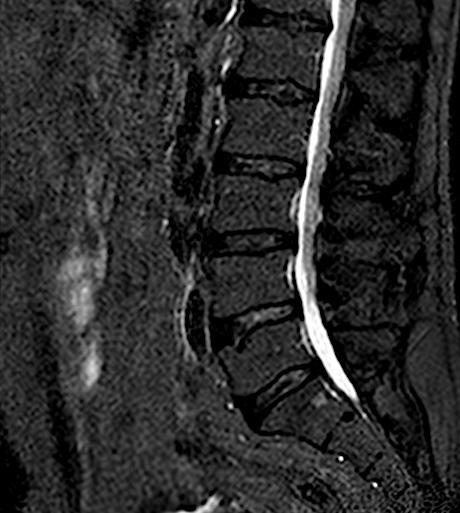

Se han marcado los ligamentos interlaminares

Las flechas rojas indican los niveles intervenidos. Obsérvese, comparando con niveles no intervenidos (flecha azul), la ausencia de ligamentos en espacio interespinoso e interlaminar

Postoperatorio

Los cambios postoperatorios son muy sutiles en la RM. Quizá en una RM dinámica (en bipedestación y extensión) pudieran apreciarse mejor.